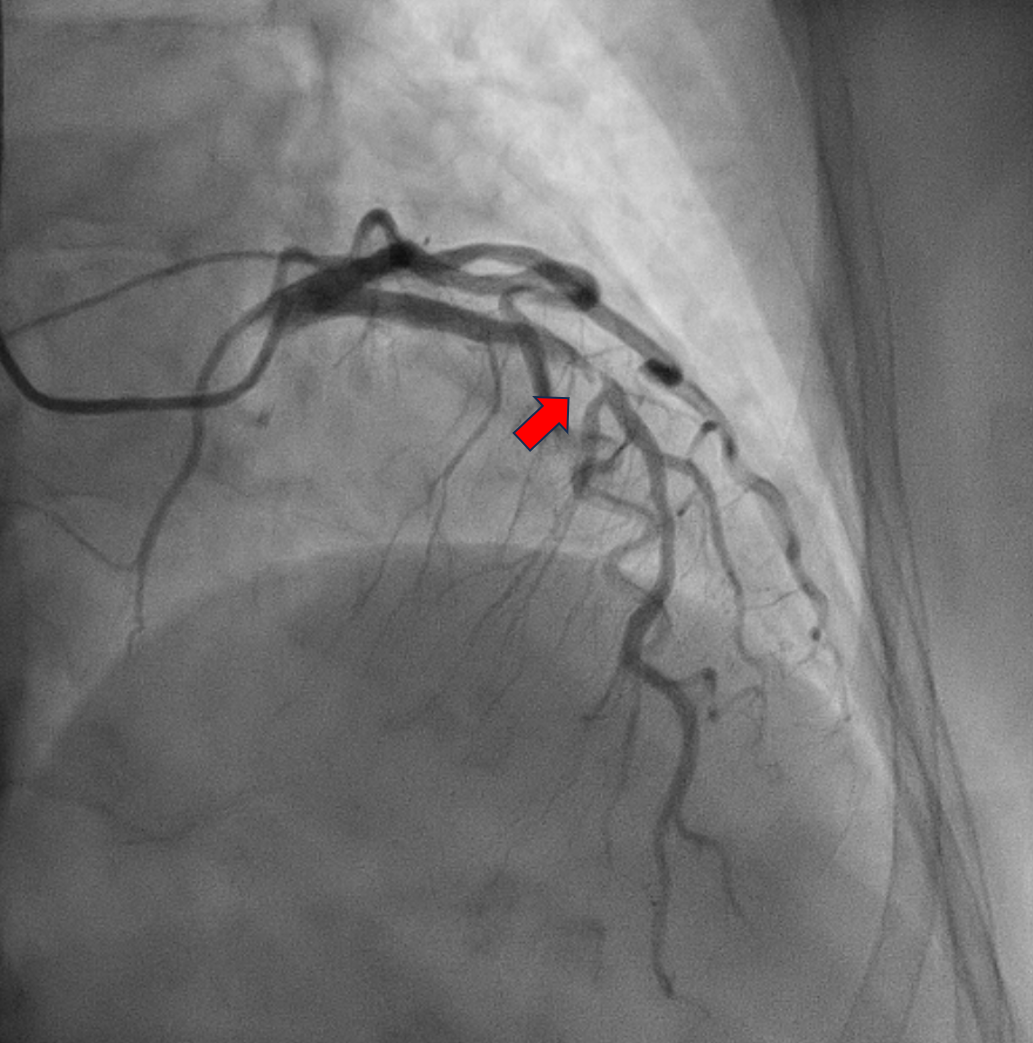

Relevant Catheterization Findings

The patient was electively admitted for diagnostic coronary angiography on August 12, 2024, which revealed single-vessel disease (SVD) with 95% stenosis in the proximal to mid left anterior descending (LAD) artery. The LAD lesion is tight and calcified. His Left circumflex vessel and right coronary vessel are normal. We proceeded with percutaneous coronary intervention (PCI) to the LAD with DCB only strategy.

The procedure was performed using a 7 Fr right radial approach. A total of 6000 units of intracoronary heparin and 300 mg of oral clopidogrel were administered. The left coronary system was engaged with a 7 Fr extra-backup (EBU) 3.5 mm guiding catheter, and the lesion was successfully crossed with a Run-through floppy wire extending to the distal LAD. Pre-dilation was performed with a 2.0 mm x 15 mm Genoss balloon, inflated to 16 atm. Intravascular ultrasound (IVUS) imaging revealed 360-degree superficial calcium at the tight LAD lesion, a vessel diameter under 3.5 mm, and a calcium score of 2. The mid-LAD measured 3.0 mm and the proximal LAD measured 4.0 mm. Pre-dilation was performed in the mid-LAD using a 3.0 mm x 16 mm Genoss non-compliant (NC) balloon, and in the proximal LAD with a 3.5 mm x 20 mm NC Emerge balloon, both inflated to 16 atm. Post-pre-dilation IVUS imaging showed cracking of the superficial calcium with vessel expansion to 3.0 mm. Subsequently, drug-coated balloon (DCB) angioplasty was performed with a 3.0 mm x 30 mm Magic Touch DCB in the mid-LAD and a 3.5 mm x 35 mm Magic Touch DCB in the proximal LAD. Final angiography demonstrated a non-flow-limiting Type A dissection with less than 30% recoil, and the procedure was successfully concluded.